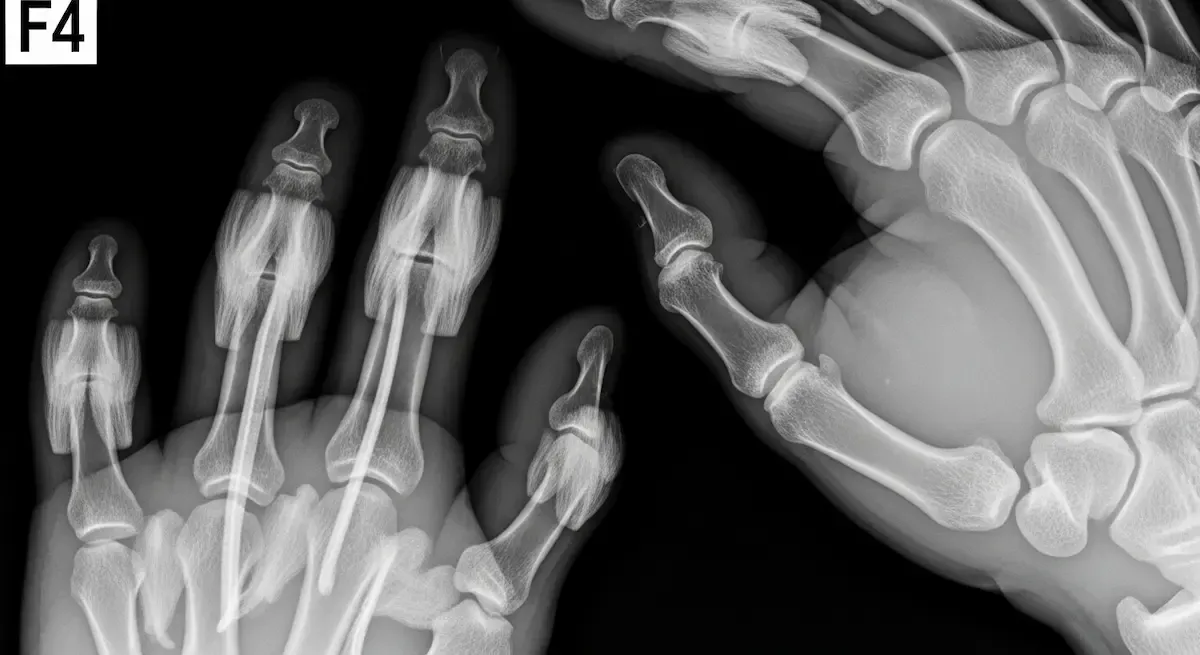

Cada dedo, com exceção do polegar, possui três articulações: a metacarpofalângica (MCF), que conecta o metacarpo ao primeiro osso do dedo (falange proximal), e duas articulações interfalângicas (IF): a interfalângica proximal (IFP) e a interfalângica distal (IFD). O polegar, por sua vez, possui uma articulação MCF e uma IF.

Todas essas articulações são estabilizadas por um conjunto robusto de ligamentos:

- Ligamentos colaterais: São os principais estabilizadores de cada articulação dos dedos. Existem dois ligamentos colaterais em cada articulação (um de cada lado), que impedem movimentos laterais excessivos, sendo cruciais para a estabilidade durante a preensão e a pinça.

- Placa volar (ou ligamento volar): Localizada na parte da palma da mão de cada articulação, esta estrutura fibrosa impede a hiperextensão dos dedos. É particularmente importante nas articulações IFP e MCF.

- Ligamentos acessórios: São ligamentos menores que complementam a estabilidade, como os ligamentos da polia, que mantêm os tendões flexores próximos aos ossos, otimizando sua função.